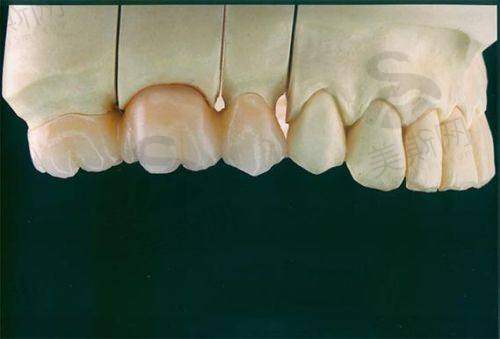

6. 全瓷美学修复:采用德国泽康、威兰德全瓷冠,生物相容性好,色泽自然,使用寿命可达15年以上。

10. 全瓷冠:德国威兰德 2800元/颗,泽康 3800元/颗